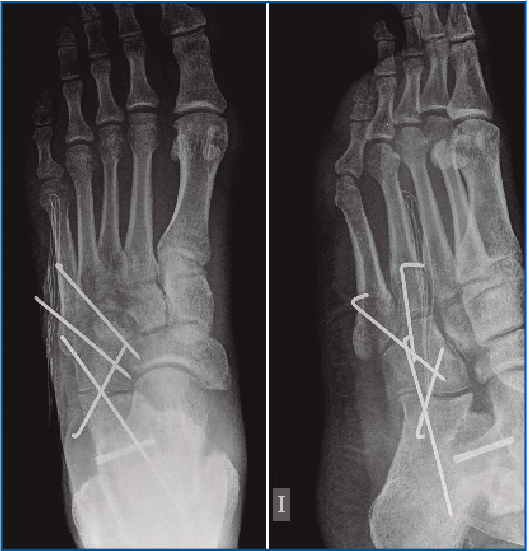

Es intervenido a la semana de la lesión realizándose, bajo anestesia raquídea e isquemia del miembro, una incisión dorsolateral desde la articulación calcaneocuboidea hasta la base del 4.º MTT. Se expuso el cuboides reflejando el extensor corto a dorsal y peroneo corto a plantar y se evidenció la desalineación del cuboides con el 4.º y 5.º MTT y el calcáneo creada por la luxación. Se realizó una reducción manual del mismo y una fijación con 2 agujas de Kirschner (agujas K) metatarsocuboideas, 1 aguja cuboideocalcánea y 1 calcaneocuboidea, realizándose al mismo tiempo una fijación de la apófisis lateral del astrágalo con un tornillo canulado (Figuras 3, 4 y 5). Se mantuvo 6 semanas inmovilizado, momento en el que se retiraron las agujas K. A la 6.ª semana, se inicia la carga con ortesis de carga hasta la 8.ª semana.

Figura 5. Imagen intraoperatoria de la reducción del cuboides y fijación con 2 agujas de Kirschner metatarsocuboideas, 1 aguja cuboideocalcanea y 1 calcaneocuboidea.

La evolución clínica y radiológica ha sido satisfactoria, permitiendo un aumento progresivo de las actividades (Figuras 6 y 7). A los 2 años de seguimiento el paciente no refiere limitaciones, con una puntuación en la escala de la American Orthopaedic Foot and Ankle Society (AOFAS) de 90.

Figura 6. Radiografía al mes de la cirugía con la correcta reducción ósea.